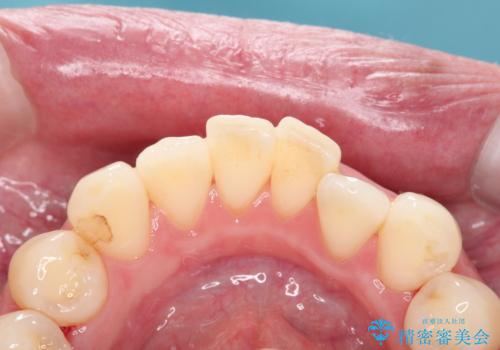

歯周病治療(歯石除去と歯磨き指導)

状態により、歯石除去の来院回数は変わります。また歯石除去をしても、ホームケアが安定していないと意味のない物となってしまう為、歯磨き指導はとても重要です。

患者様の協力がないと歯周病の進行は止められません。

歯石除去を進めていくと、歯肉が下がったり出血したり、知覚過敏が起きる事がありますので、不安にならないためにも、担当歯科衛生士の説明をしっかりと確認してくださいね。